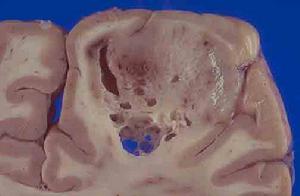

3.CT檢查 多表現為半球深部的低密度或等密度病變可有囊變和壞死出血少枝細胞瘤可見鈣化,占位效應和周圍水腫帶明顯。低惡性度腫瘤可不強化,但少枝母細胞瘤和膠質母細胞瘤多有明顯不規則強化(圖1)